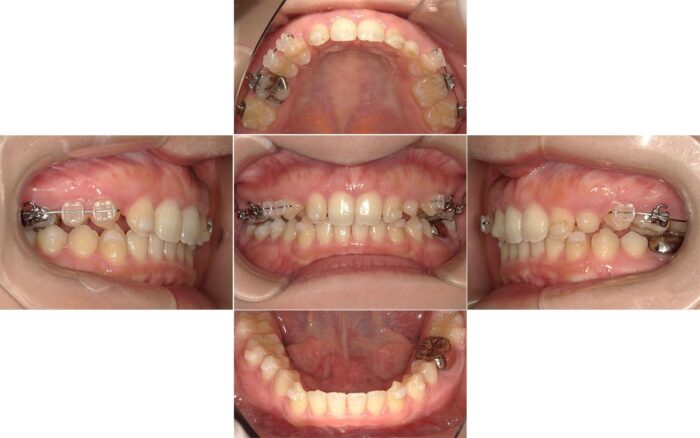

マウスピースから全体ワイヤー矯正に変更した症例

出っ歯とすきっ歯の改善を希望されて相談にいらした患者さまです。口元の突出感が気になるとのことだったので、抜歯矯正をお勧めしましたが、患者さまのご希望で歯を抜かずに治療を開始しました。

治療を始めてから半年が経過したころ、患者さまからご相談があり治療方法を変更することになりました。

やっぱり口元が気になるので歯を抜きたいです

先ほどご紹介したように、ガタガタのない歯列の歯を抜く場合、隙間を閉じるための歯の移動距離が長く、マウスピース単独だと治療に時間がかかる症例です。

隙間が閉じるまでワイヤー矯正で進め、隙間が閉じたらマウスピースに戻ってかみ合わせを調整する方針で治療を再スタートしました。

矯正治療で歯を抜くか抜かないか迷っている方へ、歯を抜く決心がついた時は早めに教えてくださいね!

歯を抜いたことで横顔の変化が大きく、気にされていた口元の突出が解消されました。

食事(特に給食)のたびにマウスピースを外すことが負担だったそうで、結局マウスピースに変更せず、最後までワイヤーで治療を行いました。

【マウスピースから全体ワイヤー矯正に変更した症例詳細】

- 主訴:口元の突出

- 診断名:上下顎前突

- 初診時年齢:12歳・女性

- 使用装置:マウスピース矯正装置(インビザライン)、表側ワイヤー矯正

- 抜歯部位:上下左右第一小臼歯

- 治療期間:2年10ヶ月

- 費用:865,000円(税込951,500円)

- リスクと副作用:痛み、歯根吸収、歯肉退縮、むし歯、後戻り